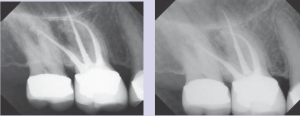

Figures 10 & 11--Postoperative views after retreatment of #3. The MB2 canal is clearly visible in Figure 11.